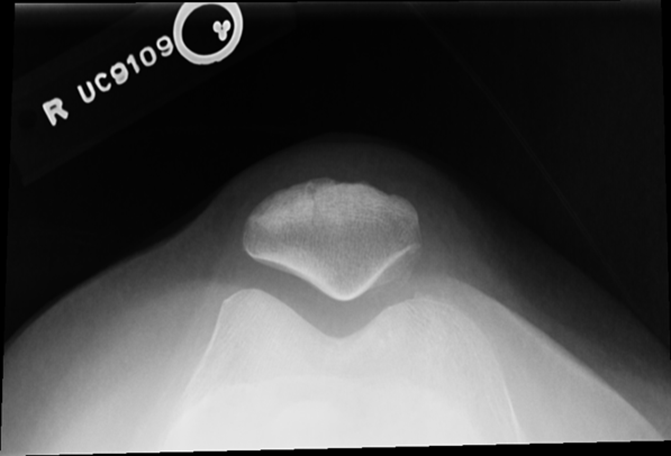

Non Trauma Patella

Erect Settegast method

(Tangential)

•Evidence of proper collimation and the presence of a side marker placed clear of the anatomy of interest

•Patella in profile

•Femoral condyles and intercondylar sulcus

•Open patellofemoral articulation

•Bony trabecular detail and surrounding soft tissues

Tibia is lower under femur underorated!

TOO MUCH TUBE ANGEL OR TOO MUCH LEG FLEXTION, Medial Rotation, larger condyle

Tibia came through joint space, patella is good!!!

Did not flex the knee enough not enough tube angle